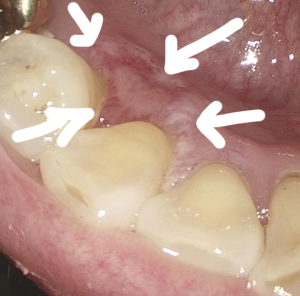

CT/MRI 등의 검사를 통해, 다행하게도 아직 하악골을 침범하지는 않은 것으로 판단된 조기의 치은암으로 진단하였고, 이 경우 변연절제술(marginal mandibulectomy)가 가능합니다.

변연절제술은 하악골을 침범하지 않았거나, 골막 침범에 국한된 수준의 조기 치은암에 적용가능한 술식입니다. 하악골 변연절제를 넘어 부분절제부터는 고도의 재건수술이 동반되어야 합니다.

수술은 치아뿌리까지 제거하되, 하악을 약 2cm이상 남겨 향후 임플란트에 대비했습니다.